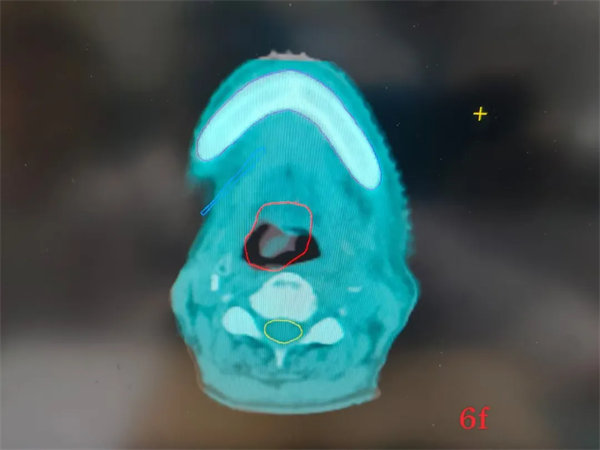

借助TOMO精準治療優勢,綜合評估后,近期,放射治療科為一例舌癌復發轉移、憋氣明顯的患者進行了放射治療,僅僅經過四次放療,老人家憋氣的癥狀就有了明顯的改善,圖像引導的結果顯示,病灶也同步在逐漸縮小。

完成放射治療后,復查CT,如下